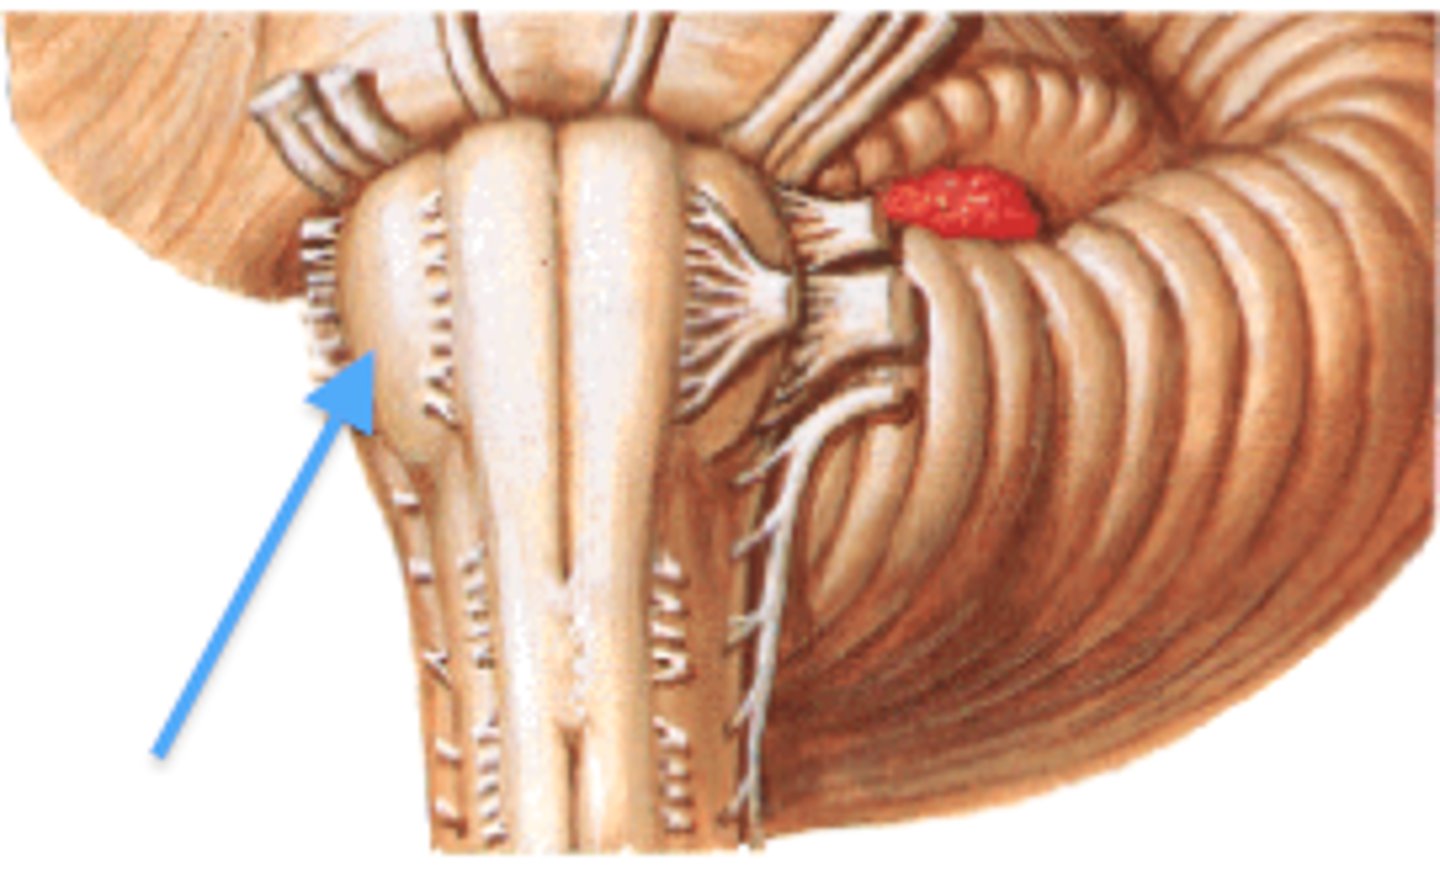

2nd largest, crescent-shaped, separates cerebrum (occipital lobes) from cerebellum (arrow #5)

falx cerebelli

seperates the two hemispheres of the cerebellum. it lies inferior to the tentorium cerebelli, separating cerebellar hemispheres (arrow #7)